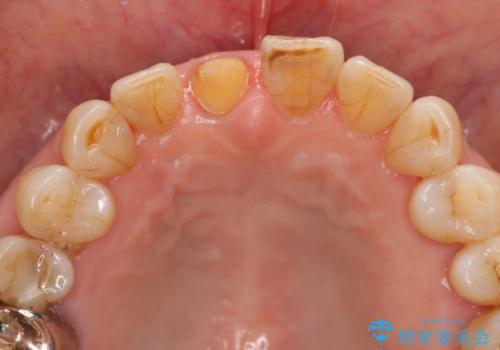

ジルコニアクラウンエクセレントについて

当法人でご提案できる最上位クラスのジルコニアクラウンです。

透明感や周囲の歯との色の調和に大変ご満足いただけました。